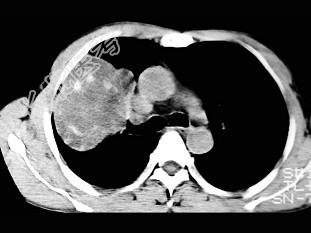

- 单项选择题根据所提供的图像,最可能的诊断是 ( )

A、肺内软骨肉瘤

B、胸膜间皮瘤

C、球形肺炎

D、机化性肺炎

E、局限性不张